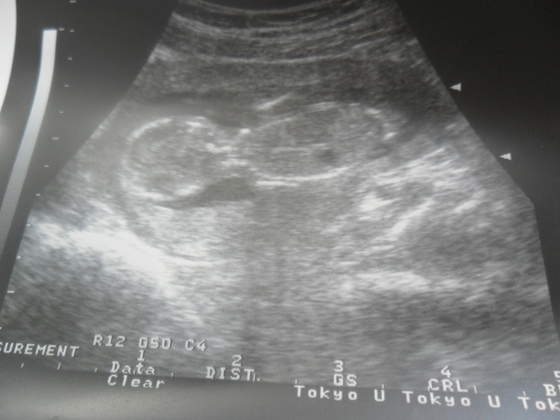

wizyta za mna. dzidziorek baaardzo ruchliwy, wszystko ma na miejscu, ale znow mi rosnie wieeelki czlowiek, z usg juz mamy tydzien wczesniej niz termin z OM ;-)

no i prawdopodobnie kolejny chlopczyk mi sie szykuje :-) nidlugo idziemy na 4d polowkowe, to pewnie wtedy sie upewnimy ;-) no ale ja tez dzis widzialam to "coś" miedzy nozkami hihihihi chyba ze sie wchlonie